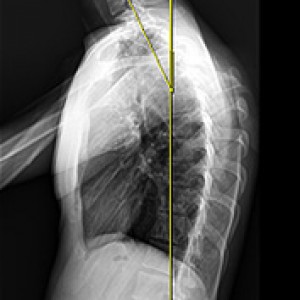

머리가 앞으로 빠질수록 목이 더 많은 하중을 견뎌야 합니다.

정상목 일자목 거북목

각도 정상 각도 15도 60도

목이 견디는 하중 5.5kg 내외 12kg 내외 28.6kg 내외